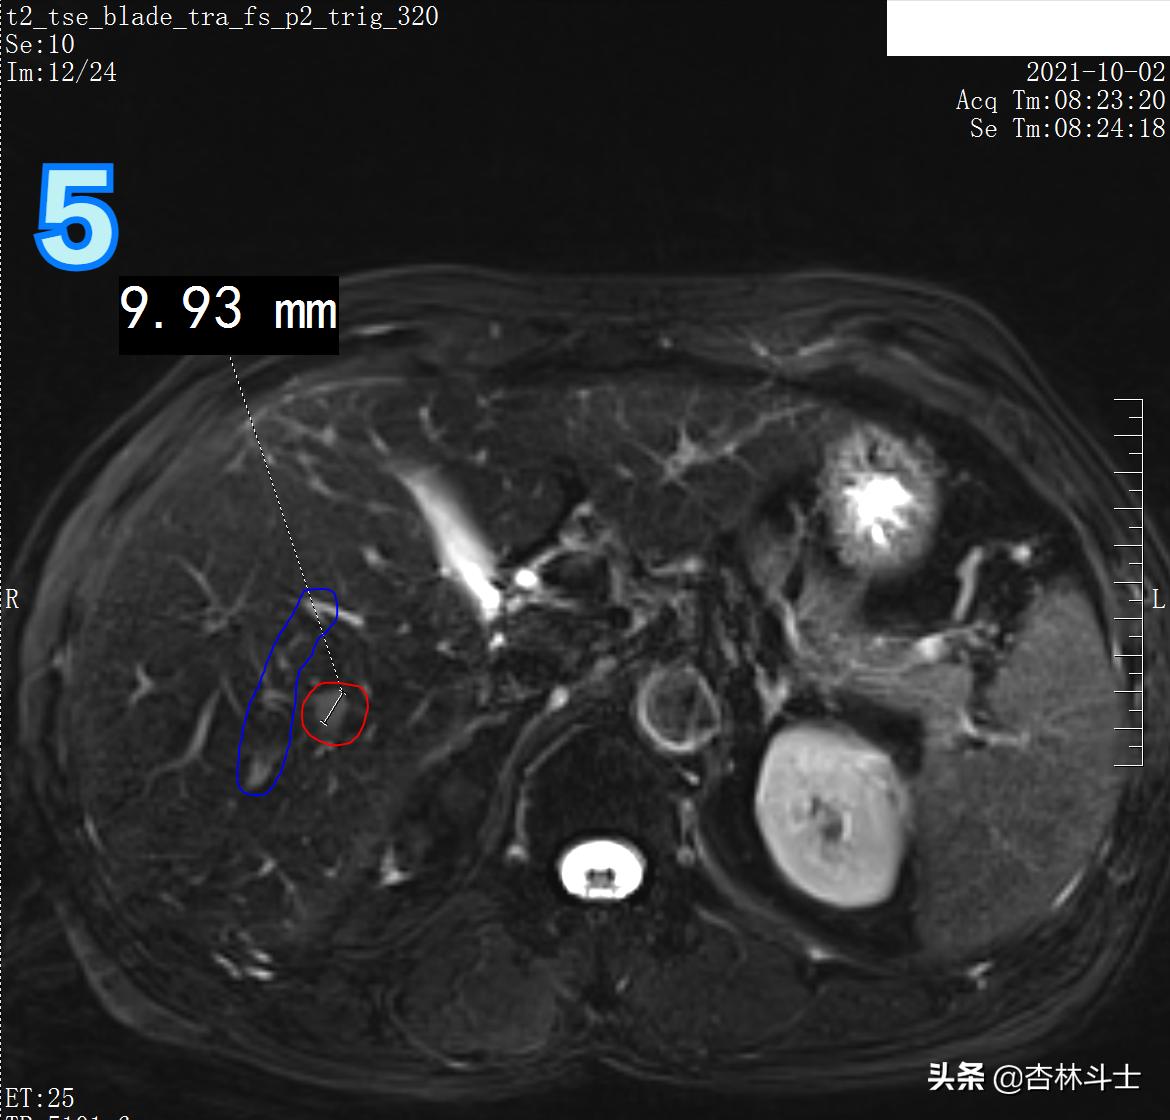

T2压脂像

图5为T2压脂像,蓝框内为三根血管,红框内为新发病灶。

图中1、椎管 2、左肾

图6、7为弥散加权像,新发病灶在弥散加权上弥散受限,呈高信号。